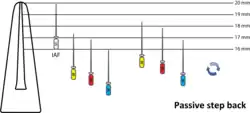

There have been a number of progressive iterations to the mechanical preparation of the root canal for endodontic therapy. The first, referred to as the standardized technique, was developed by Ingle in 1961, and had disadvantages such as the potential for loss of working length and inadvertent ledging, zipping or perforation.[12][13] Subsequent refinements have been numerous, and are usually described as techniques. These include the step-back, circumferential filing, incremental, anticurvature filing, step-down, double flare, crown-down-pressureless, balanced force, canal master, apical box, progressive enlargement, modified double flare, passive stepback, alternated rotary motions, and apical patency techniques.[14]

The step back technique, also known as telescopic or serial root canal preparation, is divided in two phases: in the first, the working length is established and then the apical part of the canal is delicately shaped since a size 25 K-file reaches the working length; in the second, the remaining canal is prepared with manual or rotating instrumentation.[15] This procedure, however, has some disadvantages, such as the potential for inadvertent apical transportation. Incorrect instrumentation length can occur, which can be addressed by the modified step back. Obstructing debris can be dealt with by the passive step back technique.[16] The crown down is a procedure in which the dentist prepares the canal beginning from the coronal part after exploring the patency of the whole canal with the master apical file.

An example of passive step back technique

An example of passive step back technique -